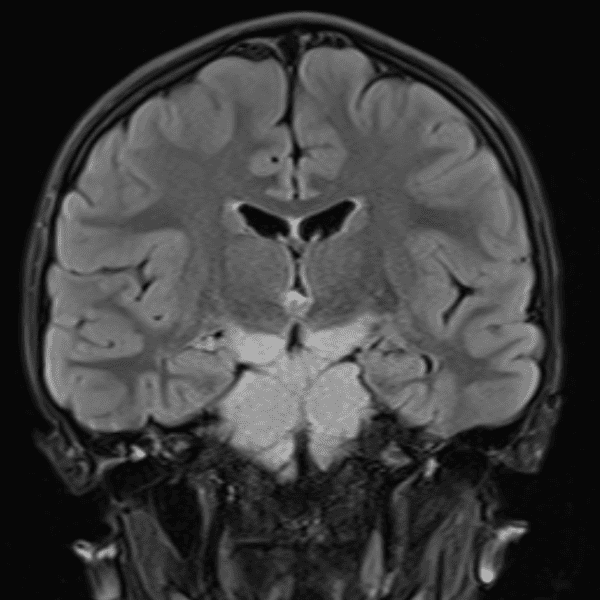

Classic Cases